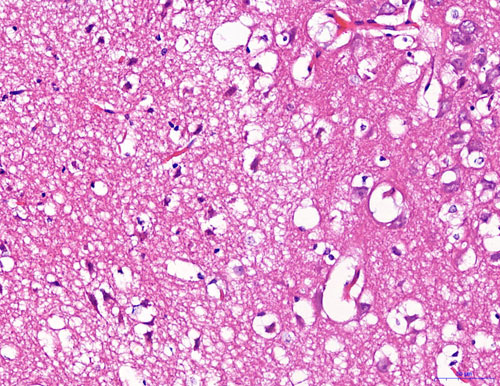

HE染色【組織病理染色】